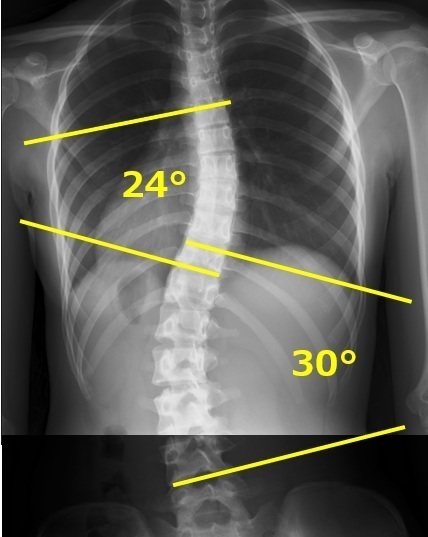

コブ角の計測・カーブパターンの評価

コブ角の計測方法

お持ちいただいたレントゲン画像からcobb角を計測します。

cobb角とは一般的に側弯症の進行を評価する角度になります。